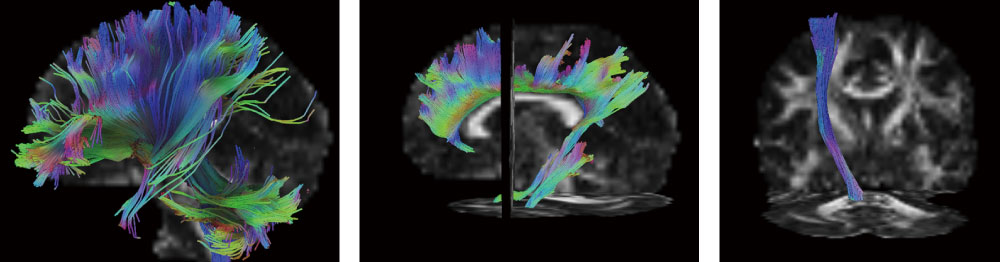

② MRIを用いた

神経線維評価とネットワーク解析

MRI(※1)を利用し、脳損傷後の神経線維束を把握することで、リハビリテーションの予後予測などに利用しています。